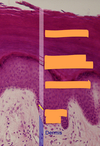

Not at all

stratum corneum stratum lucidum stratum granulosome stratum spinosum stratum basale

2

stratum corneum stratum grannulosome stratum spinosum stratum basale